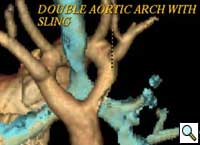

Patient was further evaluated with 64-slice MD CT angiogram which revealed double aortic arch, with balanced arches encircling the trachea and esophagus (Figure 1). The distal trachea and proximal left bronchus were compressed by the vascular ring (Figure 2, 3).

The patient underwent division of the right aortic arch through a left posterolateral thoracotomy (3rd intercostal space) approach. The right aortic arch was posterior, giving rise to the right common carotid and subclavian arteries. The left aortic arch was anterior, giving rise to the left common carotid and left subclavian arteries (Figure 4). The ligamentum arteriosum was attached to the left aortic arch and the left pulmonary artery. The ligamentum arteriosum was divided.